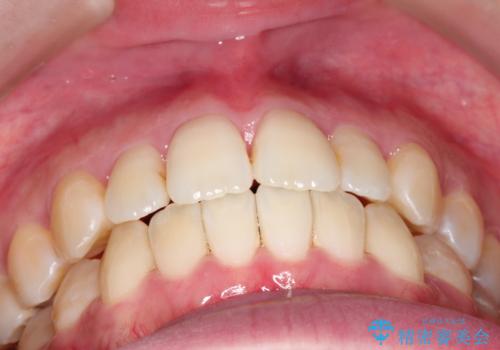

- 前歯のガタガタと、かみ合わせを改善したいとのことで来院されました。

人前でお話をするお仕事のため、装置をつけないでよいマウスピース矯正を希望されました。

下顎の歯が、上顎の歯に対して前方に位置していたので、下顎の歯を後方に移動させるのと、歯と歯の間を削りスペースを作り、歯を並べる計画としました。

お仕事の関係で使用時間が制限されるときもあり、治療期間が予想より少し長くなりましたが、装置をつけずに治療を終えることができました。